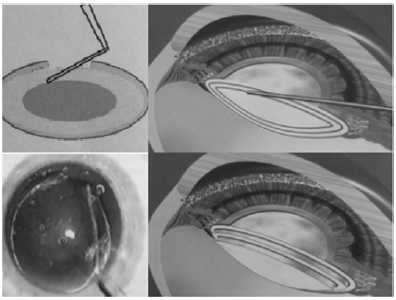

Assinale a alternativa que apresenta o passo da cirurgia de catarata que está sendo representado na figura acima.